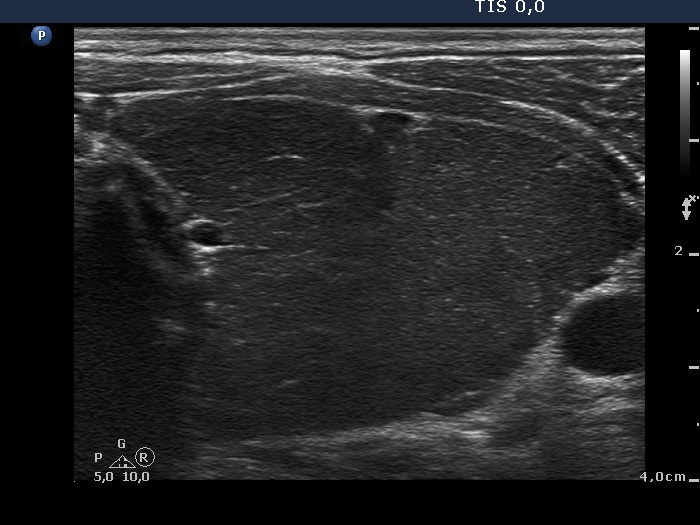

Consecutively operated patients with autoimmune thyroid disease - case 26 (1674) (ultrasonographic picture 5)

Left lobe, transverse view. The pattern is identical to that presented in the right lobe.